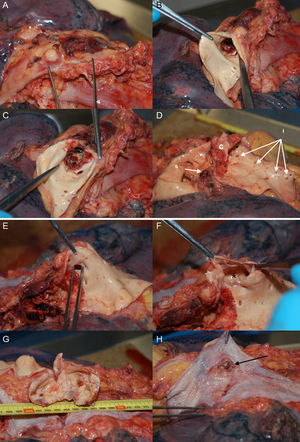

Patient 1, a 57-year-old man in NYHA class III with severe aortic regurgitation and dyspnea, required percutaneous coronary intervention before surgery. Numerous collateral vessels had complete obstruction of the aorta and a giant intercostal aneurysm below the coarctation point (Fig. 1). The aortic obstruction was treated using the technique described and a CS was implanted to exclude the aneurysm. The final outcome was very good; the gradient disappeared and there was a large increase in lumen diameter. We also performed redilation and obtained good apposition of the distal stent edge. The aneurysm could be visualized very faintly following the final injection (Fig. 2). Two days later, the end was tragic when the patient suffered a massive hematemesis and died. Autopsy showed that although the coarctation was well repaired and the stent did not have its cover, leaving the aneurysm in communication with the descending aorta. We believe that the large increase in systolic blood pressure from 70mmHg to 150mmHg after the coarctation point led to a high-pressure retrograde flow into the aneurysm. In the following hours, the aneurysmal bulge ruptured into the esophagus, with fatal gastrointestinal bleeding (Fig. 3).

(0.66MB).Figure 3.Patient 1, autopsy. A, the isthmic portion of the aorta; B and C, opening of the aorta and bare stent, without the polytetrafluoroethylene covering; D, stent extraction showing obstructive point of coarctation; (c), the left subclavian orifice (s) the orifices of the intercostal arteries, (i) the largest intercostal artery compared to the aneurysm; E, tweezers indicate the intercostal orifice; F, the opening of the orifice showing the aneurysm (*); G, opening of the aneurysm, measuring 7cm; H, esophagus with area of chronic inflammation due to the aneurysmal bulge (the arrow indicates a gap that connects to the aneurysm, found at autopsy).